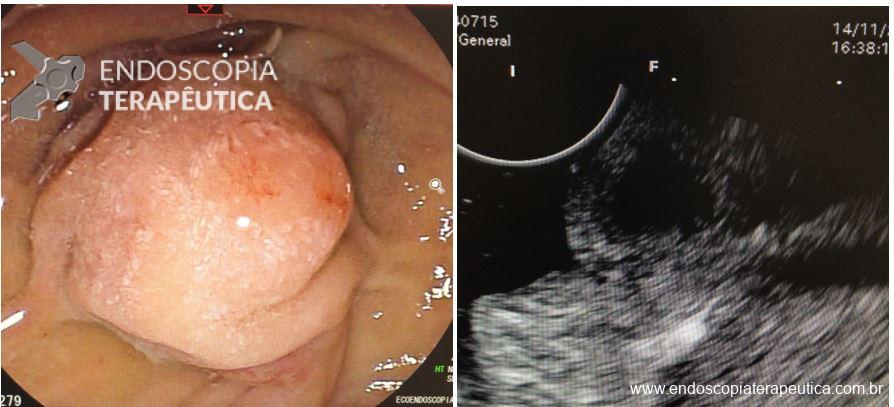

Umans e colaboradores em uma meta-análise recente chegaram a uma acurácia de 59% 7. A litíase biliar, presença de cálculos, microcálculos ou barro biliar na vesícula ou no colédoco, foi a causa mais comum, sendo responsável por 30% dos casos (Figuras 1 e 2). Em segundo lugar veio a pancreatite crônica com 12% e em terceiro o pancreas divisum com 5%. É importante salientar que em 2% dos pacientes foi detectada uma neoplasia que não havia sido diagnosticada nos exames prévios. As lesões identificadas foram neoplasias papilares intraductais mucinosas (IPMN), carcinomas de pâncreas, tumores neuroendócrinos (Figura 3), adenomas e carcinomas de papila. Outras causas menos comuns foram pancreatite autoimune, ascaridíase, coledococele (Figuras 4 e 5), anomalia da junção biliopancreática e divertículo.